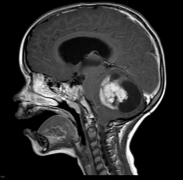

三分之二的患者存在脑积水,60%-75%的患者在出现症状时或初次治疗后不久就需要进行脑脊液分流手术。Rutka教授的丘脑胶质瘤治疗案例CT及MRI显示右侧丘脑...

丘脑胶质瘤(thalamic gliomas)是一组主要起源于背侧丘脑并可侵袭脑干、内囊、基底节区等重要功能区的脑胶质瘤总称。丘脑胶质瘤约占全部颅内肿瘤的1%...

丘脑内含重要神经核团及传导纤维,是协调、整合来自身体各部分不同的传入冲动的重要中枢,丘脑起源的肿瘤约占颅内肿瘤的1%~5%,其中以胶质瘤较为常见。...